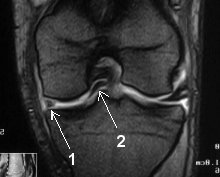

IRM du genou pour douleurs et hydarthrose récidivante: que voit-on?

Anse de seau du ménisque